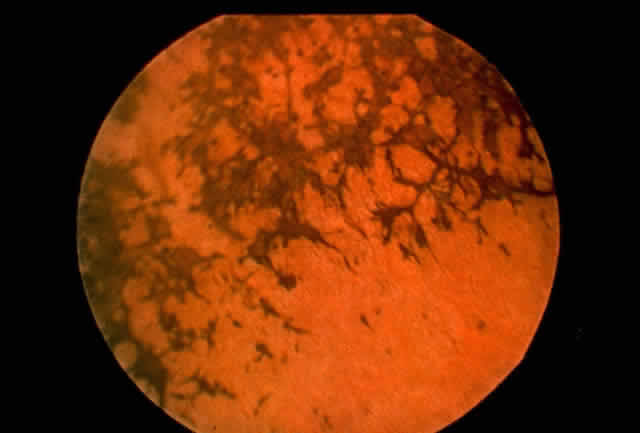

CHOROIDEREMIA

The recent discovery of the molecular defect in choroideremia is an excellent example of the power of molecular studies in advancing our understanding of disease pathogenesis. Choroideremia is a hereditary, bilateral, and progressive X-linked retinal degeneration characterized by central blindness in affected males during early adulthood. These patients have hemeralopia, decreased vision, and visual field constriction due to atrophy of the choroid and the retinal pigment epithelium (Fig. 6). One notable characteristic of choroideremia in contrast with other retinal degenerations, such as X-linked retinitis pigmentosa, is that carrier females of choroideremia have a typical fundus appearance consisting of linear retinal pigmentation with punctate area of pigment epithelial atrophy.

Fig. 6. Choroideremia. Atrophy of retinal pigment epithelium is evident.

The gene locus for choroideremia was mapped to the proximal region of Xq21.144–147 Through positional cloning, the achoroideremia gene has been identified and characterized in this region. Patients with choroideremia indeed have been found to have mutations in the putative disease gene.148–153 Up until 1993, however, very little was known concerning the biologic function of the choroideremia gene and its role in retinal degeneration. It was in the last three years, a significant breakthrough in this field was made by Seabra and colleagues,154,155 who reported that the choroideremia gene is in fact highly homologous to component A of rat Rab geranylgeranyl transferase, which belongs to a family of guanosine triphosphate-binding proteins. These proteins are believed to play important roles in the regulation of membrane transport and signal transduction. Furthermore, components of the rat Rab geranylgeranyl transferase have been found to be missing in patients with choroideremia.155 The molecular basis of choroideremia appears to be due to a defect in the membrane transport of proteins with attendant abnormalities in signal transduction. In addition, these studies suggest the exciting possibility that the genes for a host of well-characterized membrane transport proteins can be considered candidate genes for a variety of other hereditary retinal degenerations.